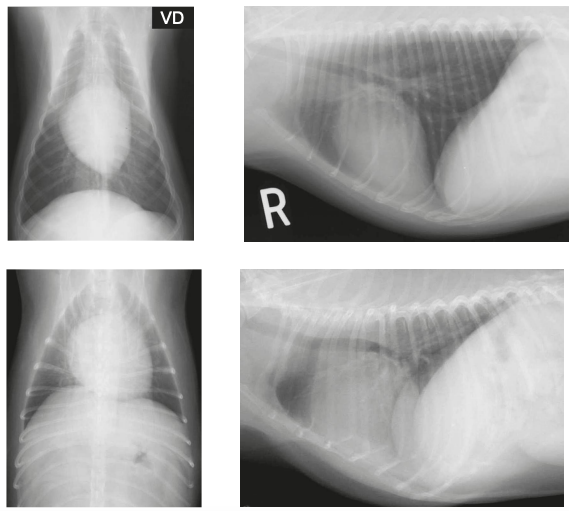

Las proyecciones se hacen en supino (ventro dorsal) para que se pueda expandir mas la caja toracica (pero hay que anestesiar generalmente)

Diferencia entre ventrodorsal o supino y dorsoventral o cubitoprono. dorsoventral es mas anatomicamente correcta ya que esta mas cerca de la placa. RECORDEMOS que la ultima parte de la proyeccion es la que toca la placa (en el caso de dorsoventral, la parte ventral)

Usamos dorsoventral para ver el corazón Ventrodorsal para ver el diafragma porque es donde se inserta el diafragma y asi podemos ver los pilares del diafragma. Se ve la proyeccion de mikey mouse

Un posicionamiento incorrecto puede dar lugar a imágenes que muestren las estructuras anatómicas de forma poco familiar, lo que lleva a diagnósticos erróneos o a la dificultad en la localización de las anomalías.